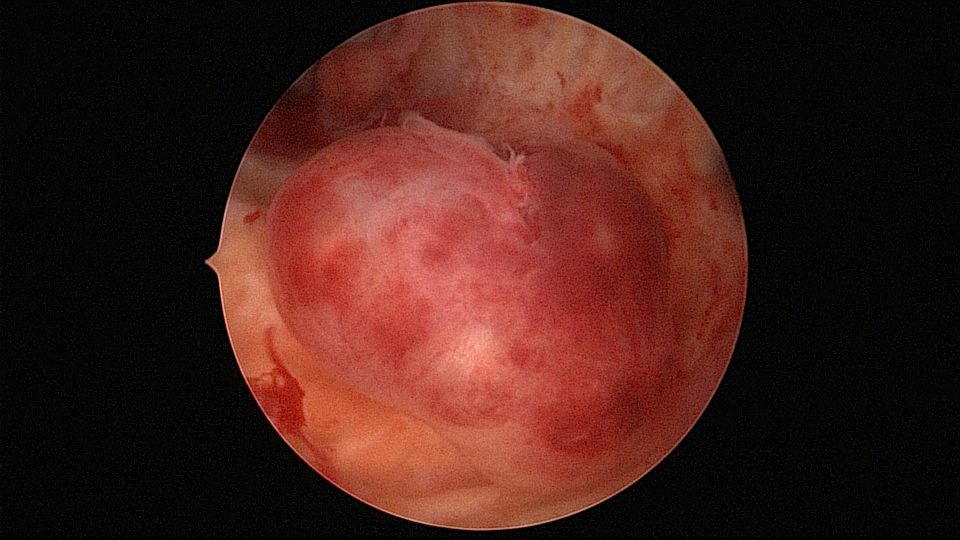

患者56岁,G2P1,顺产1次。安环16年,绝经1年,外院取环失败。宫颈外口及宫颈内口狭小质硬,分别用中弯钳及异物钳扩张,宫腔镜见宫颈管息肉2个,宫型环与宫壁嵌顿,异物钳取出,单级电针切除息肉送病检,病检结果为宫颈管息肉,宫腔未见其他异常。